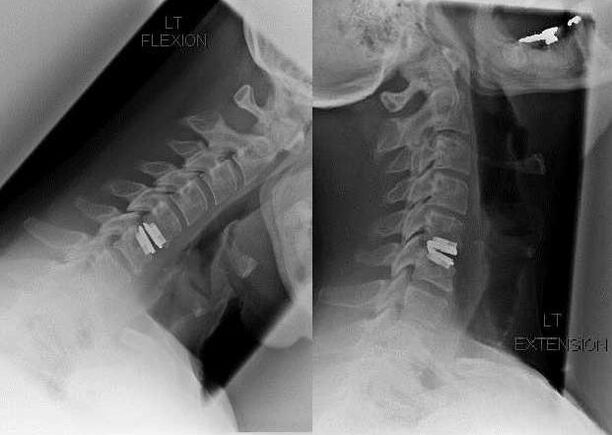

Intervención quirúrgica

Las indicaciones para la intervención quirúrgica incluyen la ineficacia del tratamiento conservador, así como las complicaciones de la osteocondrosis cervical, por ejemplo, mielopatía discogénica, síndrome de la arteria vertebral y síndrome radicular. Para descomprimir la médula espinal, los vasos sanguíneos y las raíces espinales se realizan las siguientes operaciones:

Durante la cirugía, se pueden extirpar fragmentos de hueso y ligamentos, y se pueden extirpar total o parcialmente los discos intervertebrales. Para pequeñas protuberancias herniarias, a menudo se realiza la vaporización con láser del núcleo del disco.

Después de la escisión de las estructuras vertebrales, a menudo se requiere la estabilización de los segmentos de movimiento de la columna mediante la fusión espinal o la instalación de autoinjertos óseos y dérmicos.